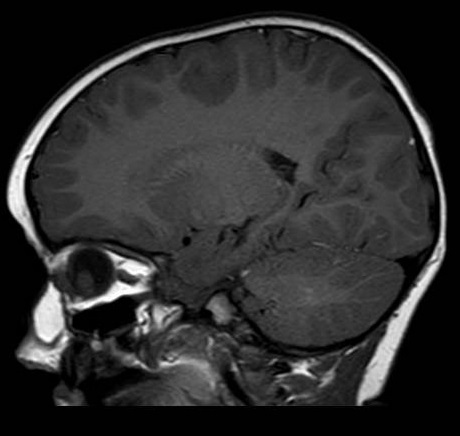

Paciente de 2 años que acude a urgencias pediátricas porque su madre refiere ver un reflejo blanco en la pupila de su ojo derecho. Niega traumatismo previo y no presenta otra sintomatología, siendo difícil valorar la posible pérdida de visión dada la edad de la paciente. Recientemente había realizado el control del niño sano en su centro de salud, sin presentar alteraciones. En la exploración se constata leucocoria periférica en ojo derecho, con reflejo rojo central. Se solicita valoración por Oftalmología, quienes realizan una ecografía ocular, objetivando una masa intraocular (Figura 1). Posteriormente, en seguimiento por Oftalmología y tras la realización de las pruebas de imagen correspondientes, se confirma el diagnóstico de retinoblastoma.

Figura 1. Ecografía ocular